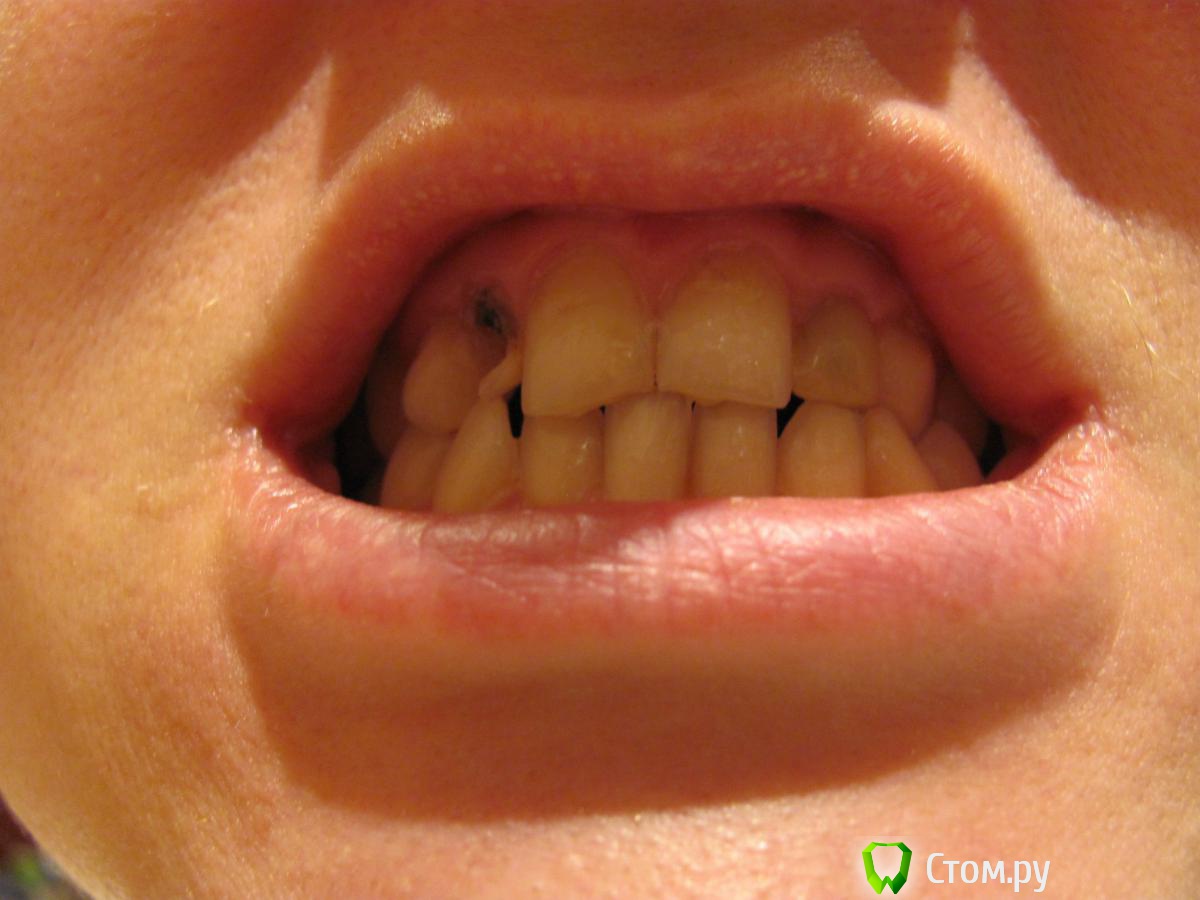

broxi Опубликовано 1 октября, 2014 Поделиться Опубликовано 1 октября, 2014 У меня молочные двойки, которые в 18 лет первый раз отреставрировала. Потом они отваливались периодически из-за неправильного прикуса. Сейчас мне 32 года. И вот отвалилась правая двойка. Возможности реставрировать, говорят, нет. Корешок совсем маленький, не за что зацепиться. Места под имплантат нет. Предлагают 1,5-2 года поносить брекеты, расширить место и вставить имплантат. Заодно то же самое проделать с левой двойкой, которая тоже рано или поздно отвалится. Вроде бы тройки-клыки тоже молочные, но они никогда не реставрировались и выглядят более устойчивыми. Но если носить брекеты, они вряд ли выживут. Получается 4 имплантата. Указанный выше вариант для меня пока крайне нежелателен. Какие есть еще возможности? Я подумываю над тем, чтобы просто удалить обломившуюся двойку. Подвинется ли со временем тройка-клык на место этой двойки естественным образом? Или может ей как-то помочь… Клык у меня не совсем похож на клык, сильно закругленный книзу. Может, ничего будет смотреться? За "голливудской улыбкой" не гонюсь, хочется по-максимуму сохранить свои зубы и избежать брекетов и имплантатов. Можно еще потом замаскировать клык под резец или винир поставить? Ссылка на комментарий